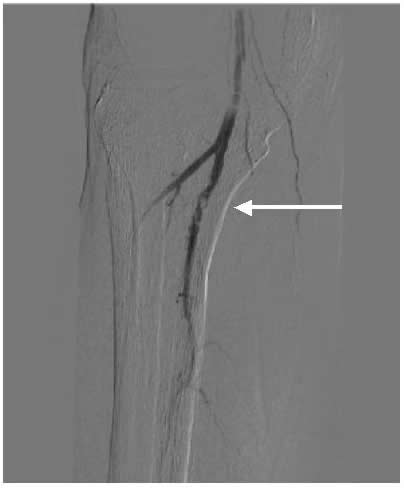

Case 3: An 81-year-old male with rest pain. The patient underwent angiography via an antegrade approach, which revealed extensive

![]() |

| Figure 3A |

| Figure 3B |

| Figure 3C |

calcific lesions of the superficial femoral artery (Figure 3A) and a lesion in the tibio-peroneal trunk (Figure 3B). The SFA lesions were debulked with a laser and the patency restored with Viabahn stents (Figure 3C). The tibio-peroneal represented the sole run off and was left as we were worried about creating a disaster if the lesion ruptured or dissected. ABI increase from 0.19 pre-procedure to 0.55 post and the patient is now able to ambulate with manageable claudication. Options to treat the more distal lesion could involve using a distal protection device and coronary balloons and/or stents.